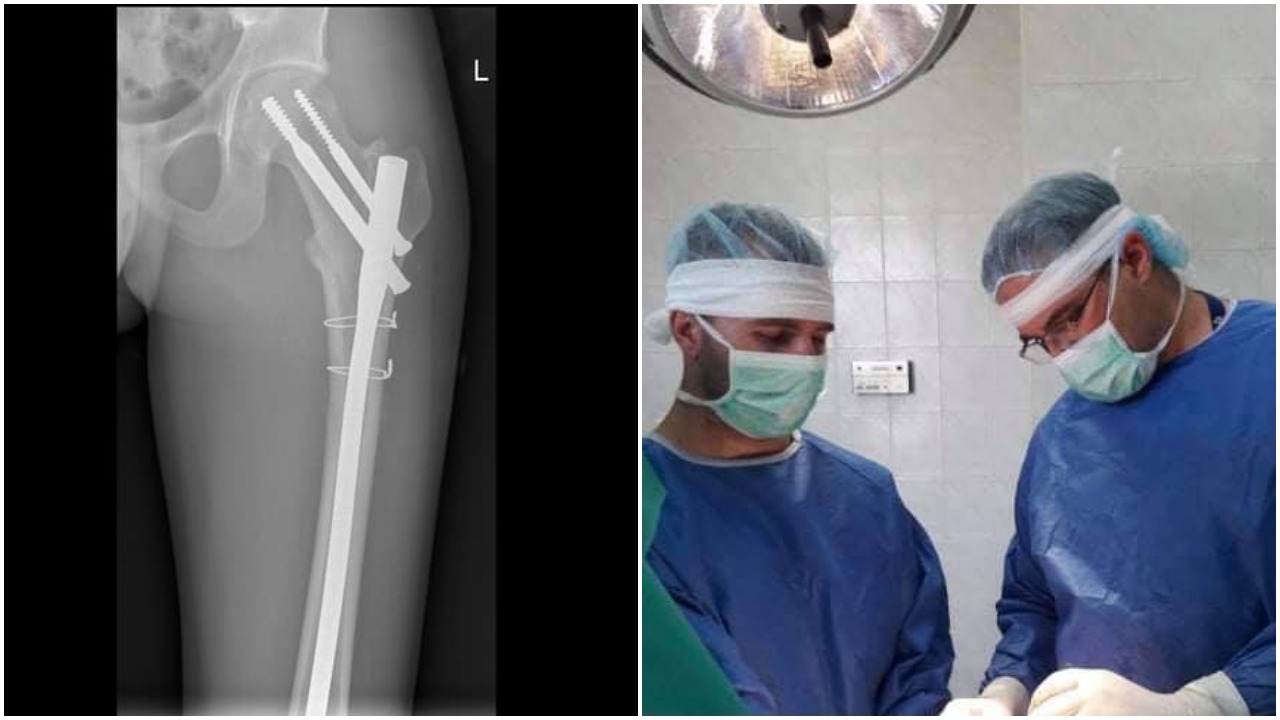

Травматологът доктор Кристиан Григоров е един от лекарите, които посрещат критичните случаи в спешното отделение на Пирогов. Пострадали в катастрофи, падания и сложни счупвания за него са ежедневие. Казва обаче, че през последната година тежките случаи намаляват: „Пандемията определено има роля за това. Ограниченията оставиха хората по домовете им. Особено възрастните, които са най-дисциплинирани и така спадна броя на инцидентите”.

Все пак доктор Григоров поема немалко спешни случаи, в които се оказва, че пациентите са с положителен тест за SARS-COV-2, съобщават от болницата. Той и колегите му обаче не се страхуват. С необходимите предпазни средства те предприемат неотложните операции. „По-голямата част от тези пациенти се възстановяват успешно. За съжаление, имаше и такива, при които се получиха усложнения, свързани с COVID-19”, разказва травматологът.

Пациентите,  претърпели травма и ортопедични интервенции са с понижен имунитет, особено тези които са загубили повече кръв. При тях спазването на мерките трябва да бъде с двойно по-голямо внимание.